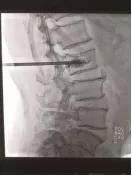

手術(shù)中情況

4月21日,我院骨科孫守全專家小組為老人進(jìn)行了PKP手術(shù),術(shù)后當(dāng)天老人腰背部疼痛銳減,己能坐起吃飯。術(shù)后第二天就能下床大小便,生活已能基本自理。七天后,老人順利出院!按照常規(guī)治療方法,需臥床三個(gè)月,還有可能出現(xiàn)尿路感染、肺部感染等等一系列并發(fā)癥。這結(jié)果與現(xiàn)在相比真有天壤之別!據(jù)了解,PKP手術(shù)為脊椎的微創(chuàng)手術(shù),手術(shù)時(shí)間短、創(chuàng)傷小,出血少,止痛效果明確,恢復(fù)比較快。尤其是對(duì)于高齡衰弱的患者而言,采用PKP手術(shù)治療,患者承擔(dān)的手術(shù)風(fēng)險(xiǎn)極大地減少,并且避免了長(zhǎng)期臥床所導(dǎo)致的潛在并發(fā)癥。但該手術(shù)部位鄰近脊柱總神經(jīng),需要施術(shù)者嫻熟的手術(shù)技巧和細(xì)心大膽的手術(shù)操作。我院骨科在濰坊市較早引入椎體成形術(shù),目前已經(jīng)為近千名老人解除了"腰痛"病痛。